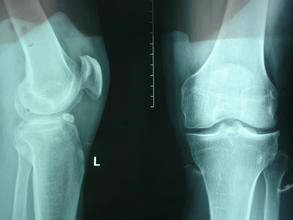

(图:治疗前刘先生膝关节内翻较为严重)

检查结果显示:血沉87mm/h,抗链球菌溶血素“O”427 IU/ml,C反应蛋白32.31mg/L;类风湿因子阳性,抗CCP抗体阳性,抗ENA抗体阴性;X线显示膝关节间隙变窄,关节出现变形。

(图:刘先生复查时所拍摄图片)